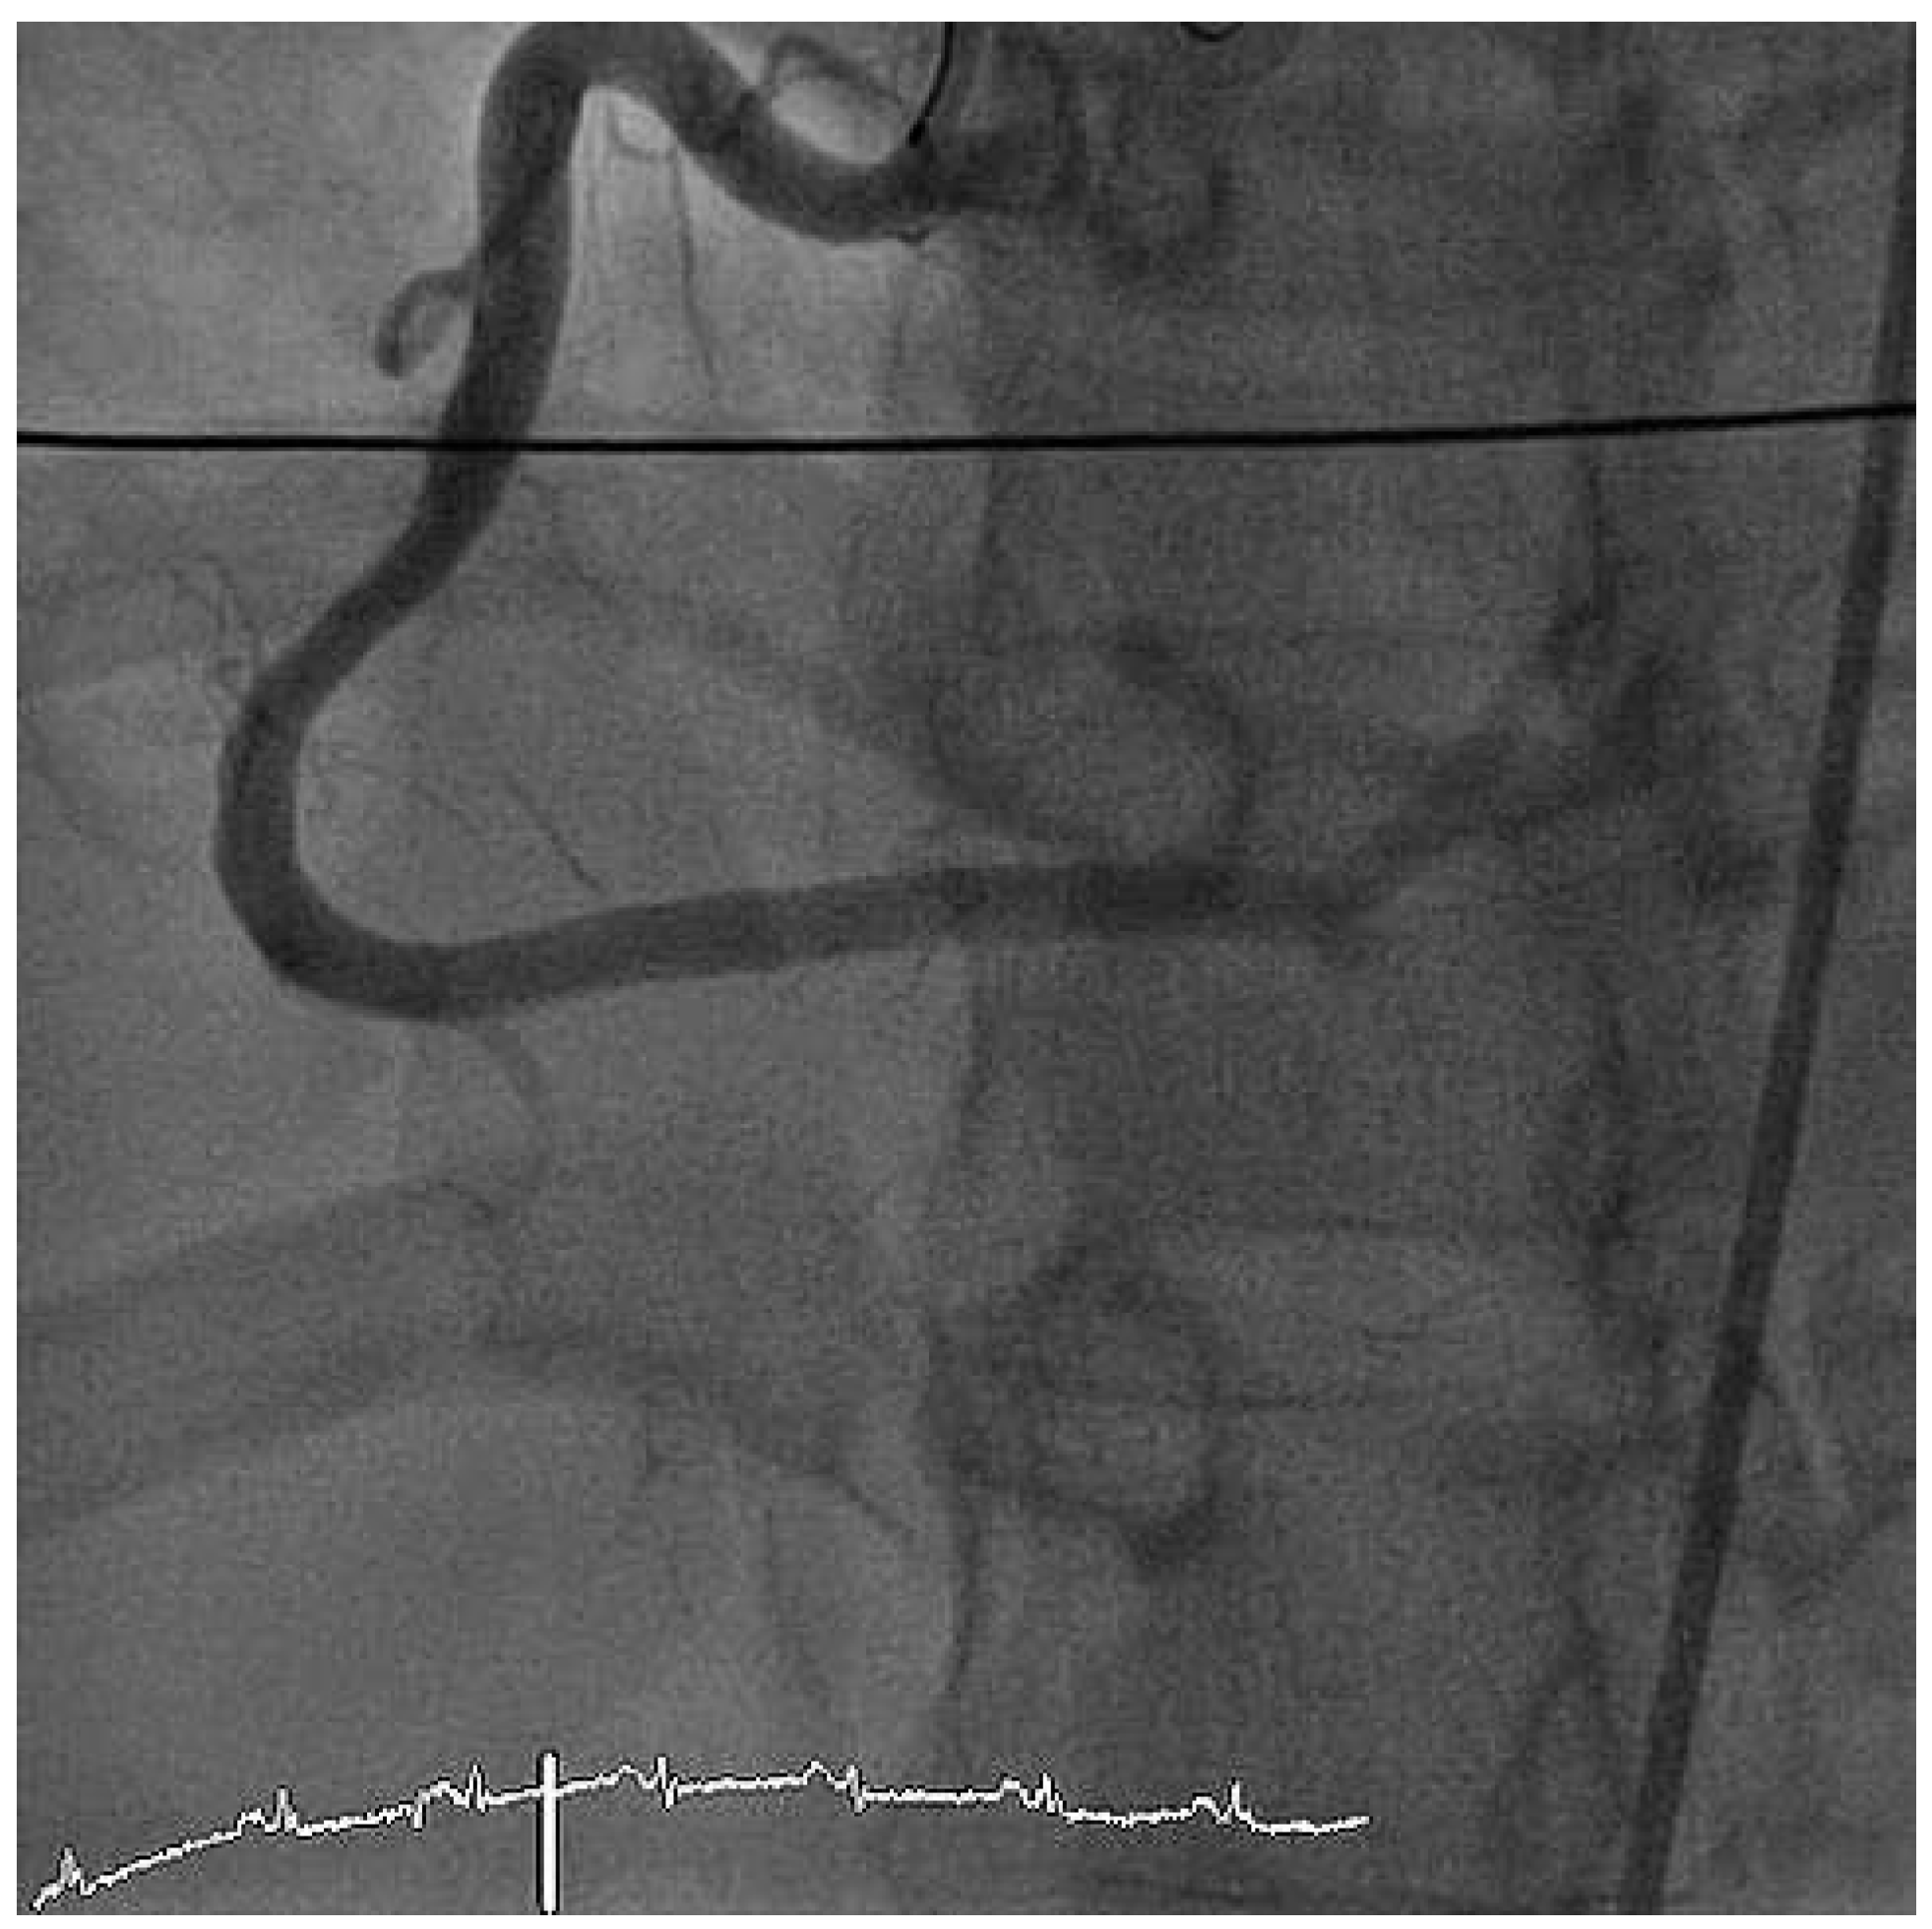

Furthermore, the right coronary artery showed a subtotal thromNo botic occlusion (Figure 3). Prior to the local treatment, a bolus of heparine 5000 IU and Abciximab were administered due to the heavy thrombus load. Thrombus aspiration was performed using an aspiration-catheter (Export AP, Medtronic) in all three coronary vessels. Due to persistent thrombotic material in the mid LAD, two low-pressure balloon inflations were done with a good end result (Figure 4 and Figure 5). There were no periprocedural complications. A treatment with life-long aspirin, one-year prasugrel, Betablocker and ACE-Inhibitor was initiated. The next day, a transesophageal echocardiography demonstrated improved LV-function (EF 50%) without evidence for an intracardiac thrombus or a patent foramen ovale (PFO).

Figure 3. LAO cranial view showing right coronary artery with subtotal thrombotic occlusion.